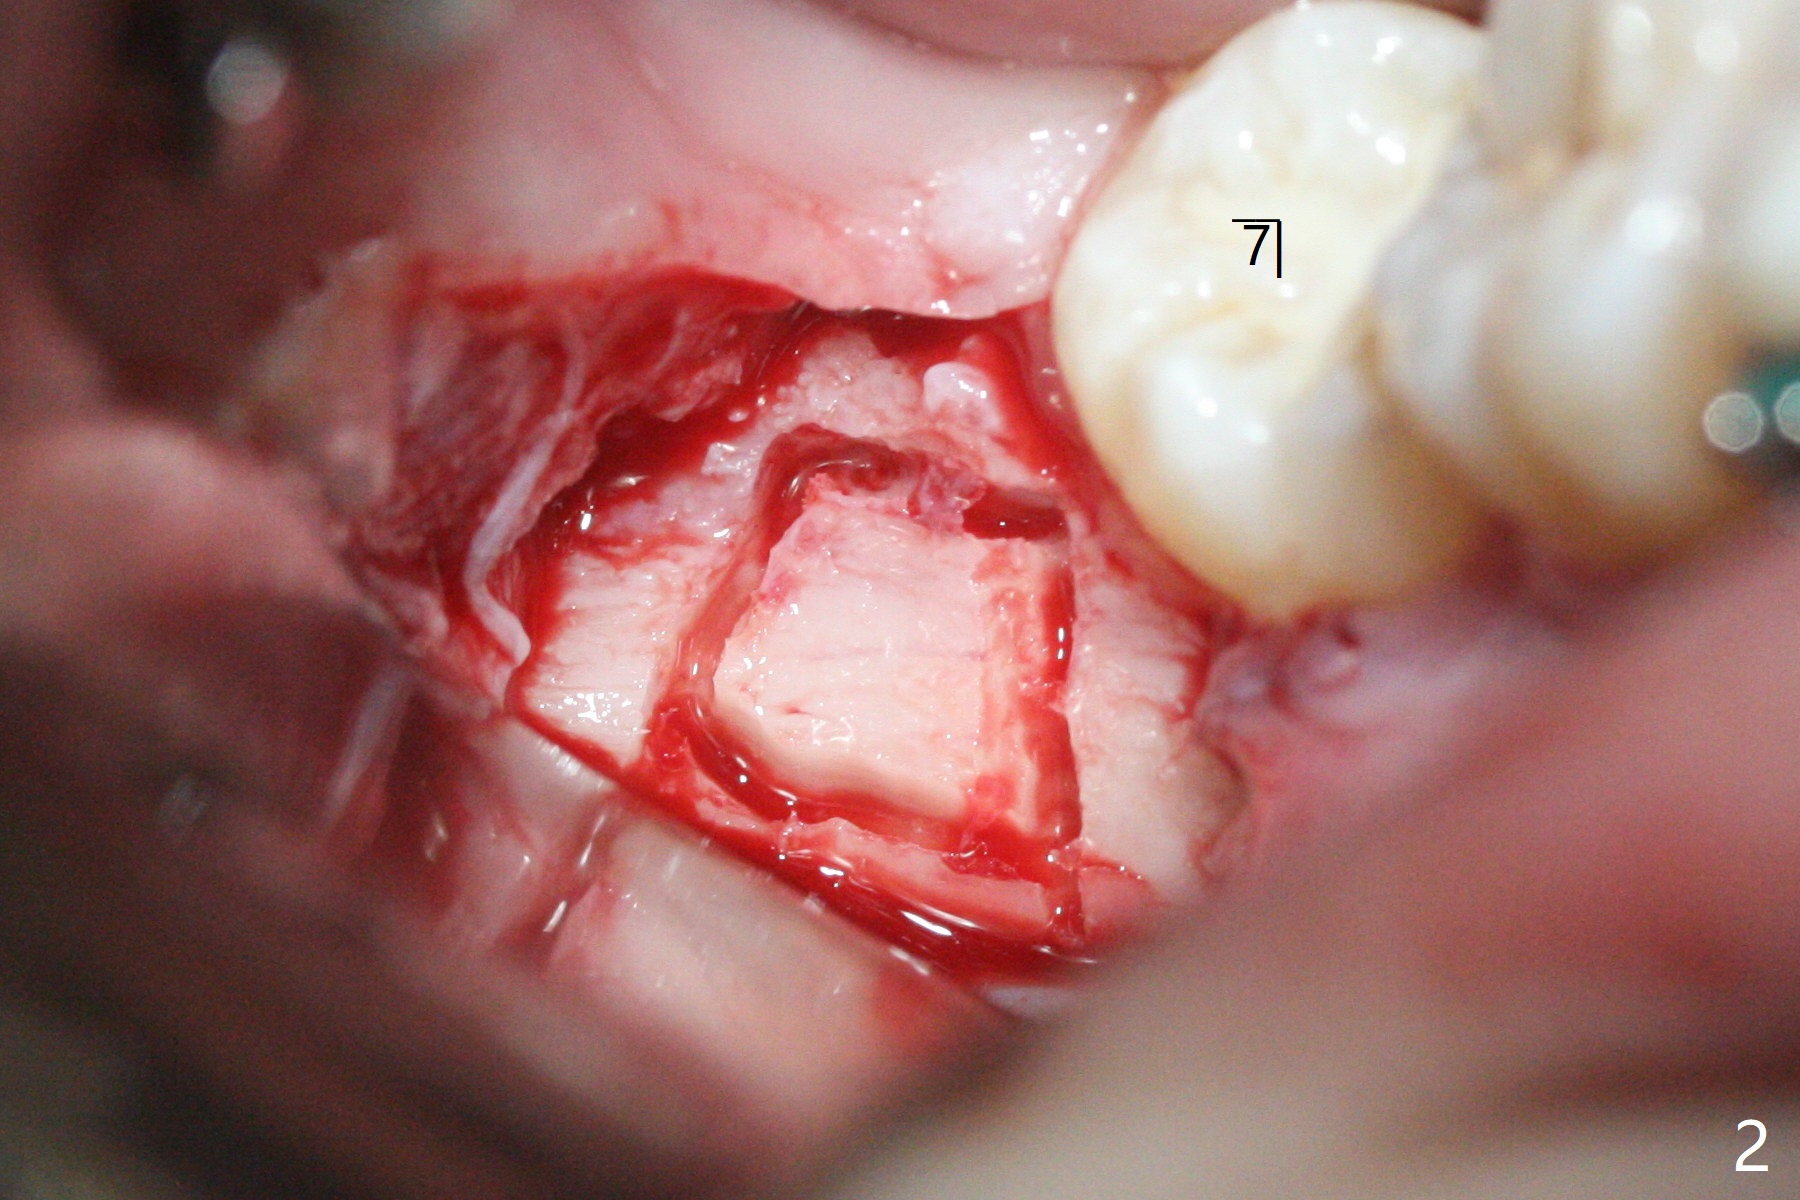

13岁男在矫正医生诊所矫正三年(上中切牙牙根短,图一),转来拔除下颌智齿以助于第二磨牙upright。左侧先拔除,切除三个小块颊侧骨板,保留其中一个与异体骨一起植入牙槽窝近中部分。右侧拔除时,索性切除一个大块颊侧骨板(图二),智齿拔除后,近中牙槽窝放置异体骨(皮质,图三,五:*),远中胶原塞(C),放回颊侧骨板(图四)。Return to Plug Xin Wei, DDS, PhD, MS 1st edition 11/03/2020, last revision 11/03/2020